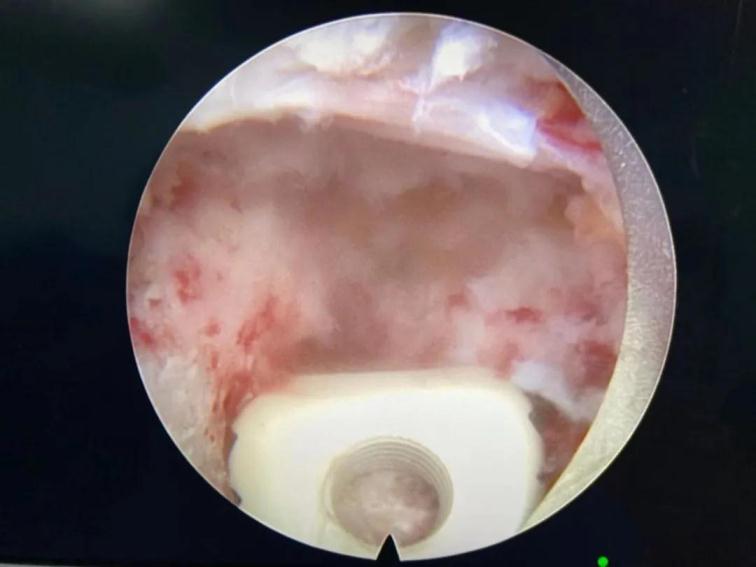

鏡下椎間融合

與傳統(tǒng)的腰椎后路開放減壓手術(shù)及通道下的MIS-TLIF手術(shù)相比,經(jīng)脊柱內(nèi)鏡后路腰椎ENDO-TLIF手術(shù),創(chuàng)傷更小,神經(jīng)根及硬膜囊顯露清晰,且最大限度的保護了脊柱骨骼、韌帶及肌肉的完整性,對脊柱運動單元穩(wěn)定性影響較小,術(shù)后患者感受更佳,康復(fù)更快。目前,該患者術(shù)后癥狀消失,已經(jīng)能夠行走自如,對治療效果非常滿意。